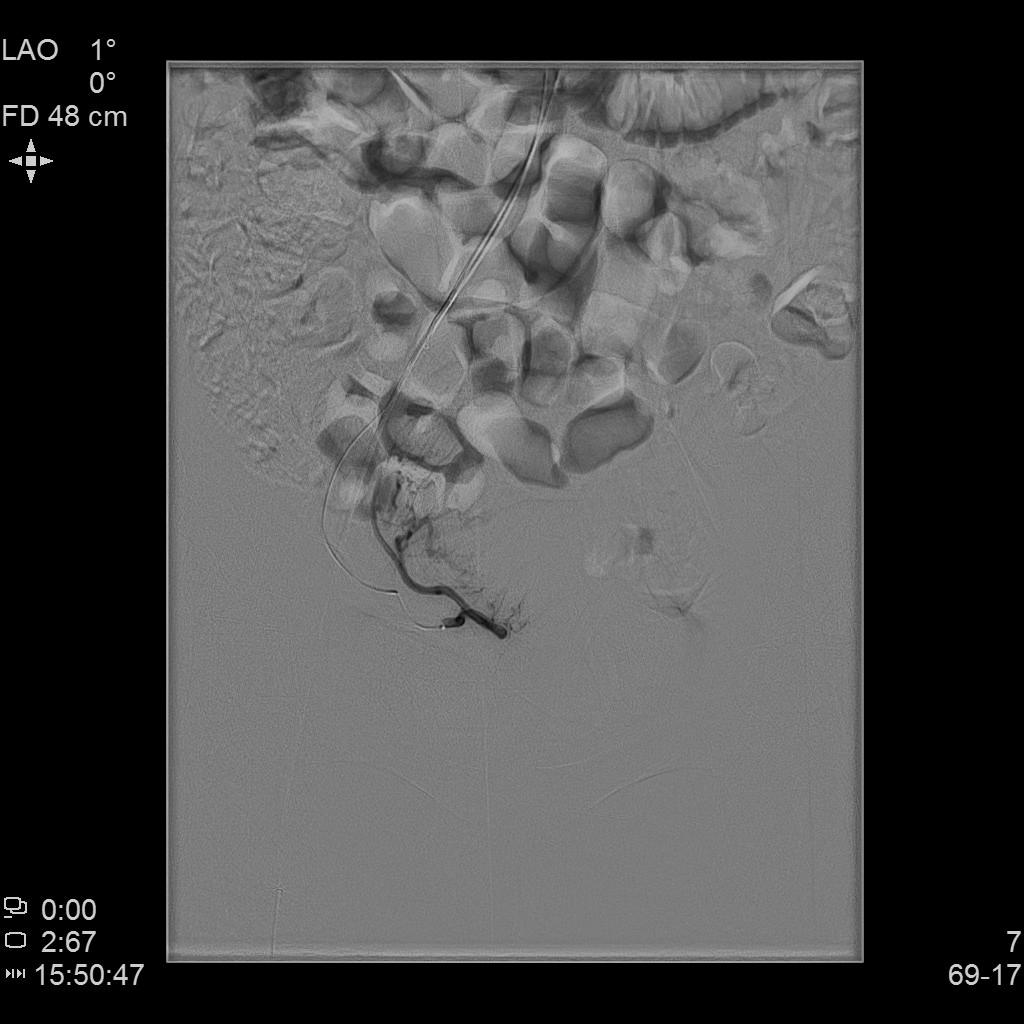

左侧子宫动脉造影